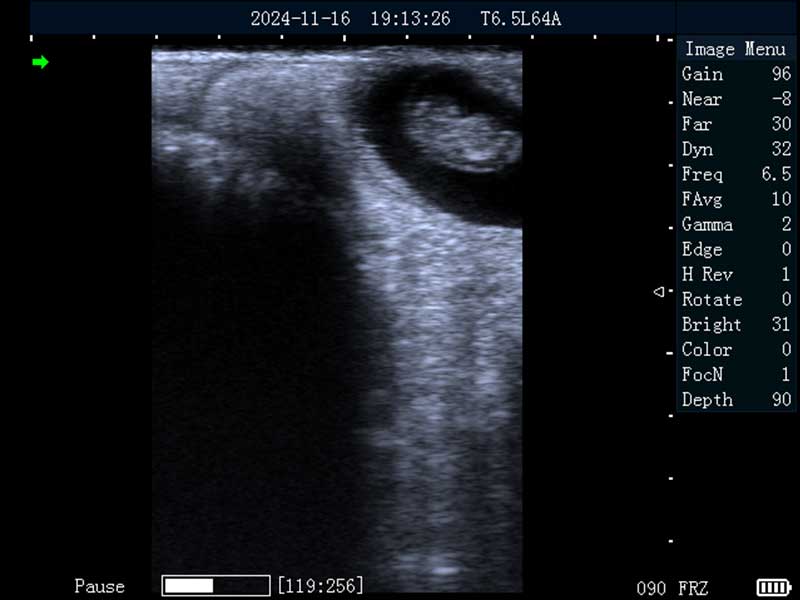

马妊娠30日龄

马妊娠26日龄